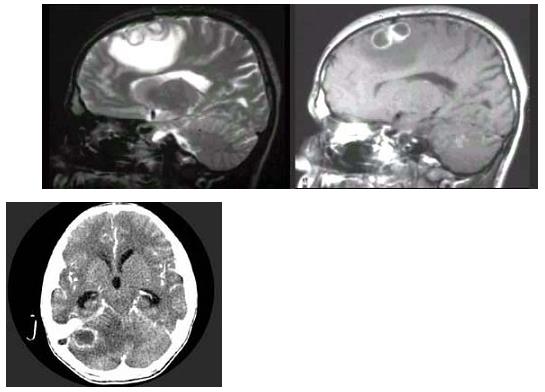

男,36岁,1周前出现全身发热、头痛、乏力,经过对症治疗病情好转,随后再次出现头痛,伴有恶心、呕吐,急到医院检查,MRI检查如图,最可韶的诊断为()。

A:星形细胞瘤

B:转移瘤

C:脑脓肿

D:脑梗死

E:脑内血肿